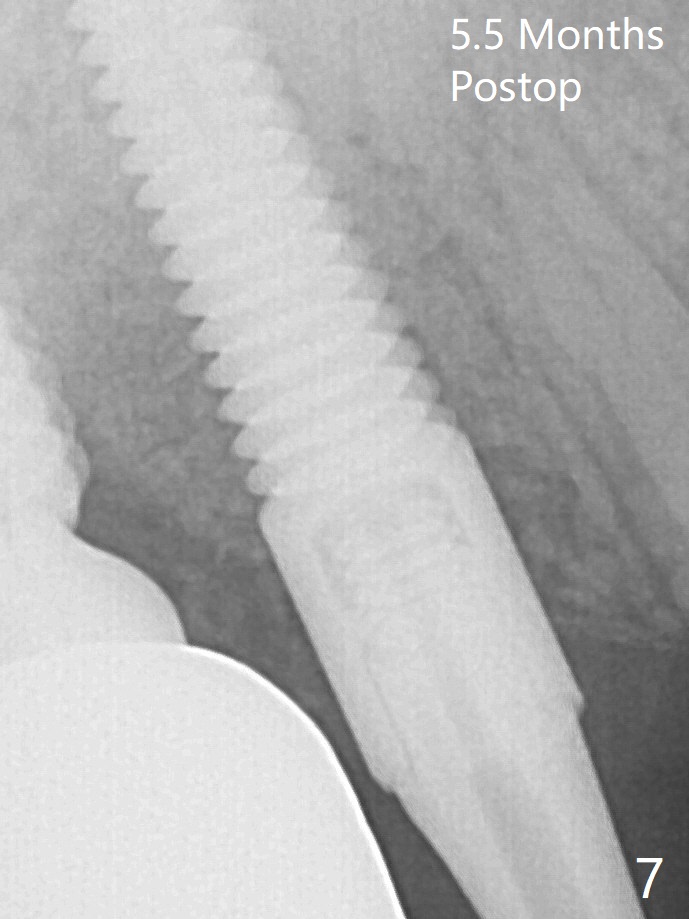

A 4x14 mm dummy implant is placed free hand (Fig.1). Following initial placement of a final 4x17 mm implant and bone graft (Fig.2 *), the crown and abutment of #3 and the guide are reseated for correct implant trajectory. The guide has to be removed for final depth control of the tissue-level implant. More bone graft is inserted mesial of #4 implant with a 3.5x5 mm abutment (Fig.3 *). The implant at # 4 seem to have osteointegrated, especially mesial, nearly 5.5 months postop (Fig.7,8).